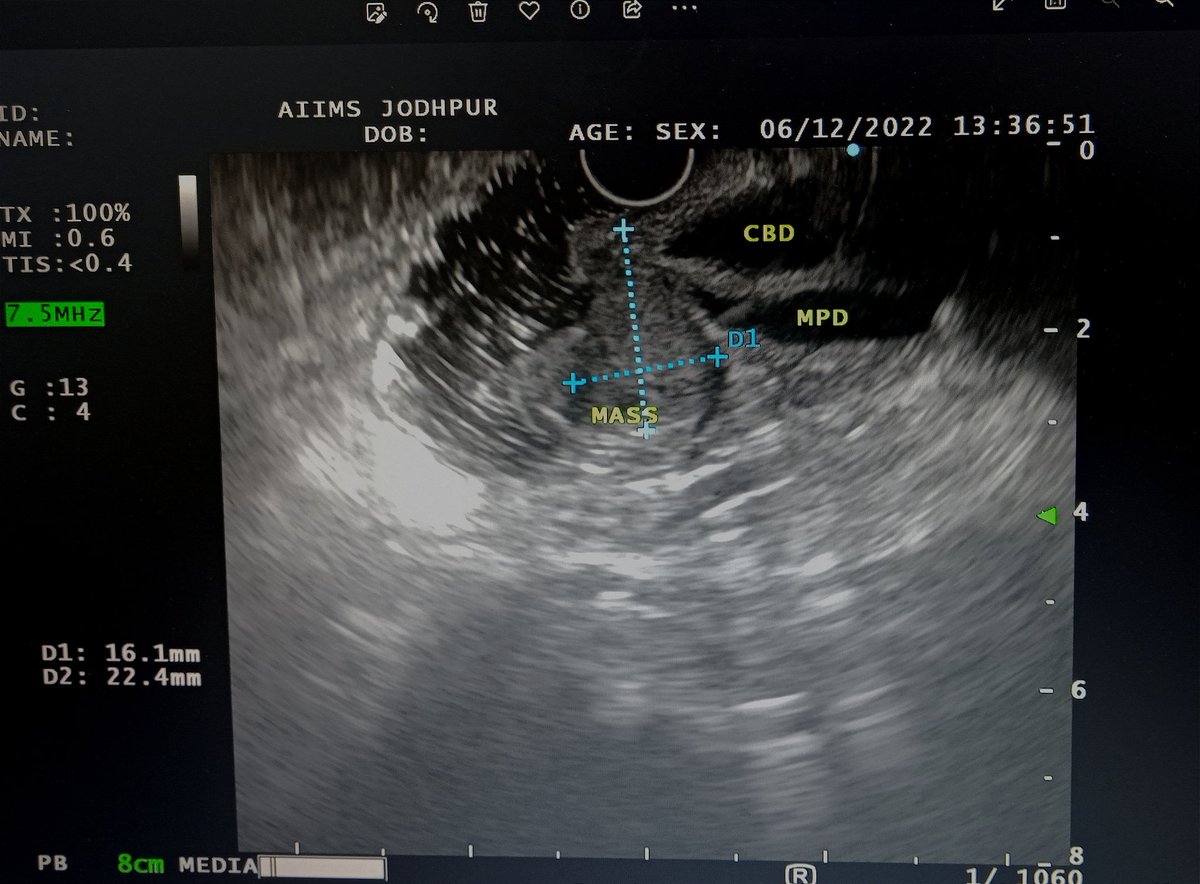

Yet another first for our centre and Rajasthan. First case of EUS guided Choledochoduodenostomy (CDS) done Department of Gastroenterology #AIIMSjodhpur @AIIMSJOfficial